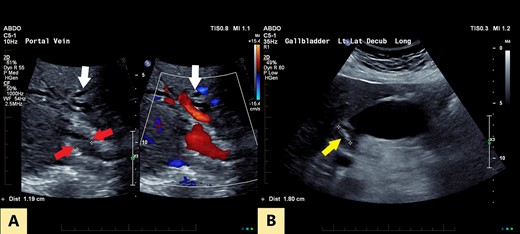

An ultrasound of the abdomen revealed a large gallstone in the gallbladder neck measuring 36 mm with mild biliary dilatation (Fig. 1). Magnetic resonance cholangiopancreatography (MRCP) revealed an irregular long stricture of the extrahepatic bile duct beginning distal to the primary biliary confluence, involving the common hepatic duct for a distance of 20 mm (Fig. 2). A multiphase liver magnetic resonance imaging was performed which confirmed a malignant appearing stricture of the common hepatic duct and showed an ill-defined soft tissue lesion in the porta hepatis between the gallbladder neck and the common hepatic duct (Fig. 3). Her Ca 19.9 was 160 kU/L (ref range < 35 kU/L).

(A) Transverse oblique US reveals segmental wall thickening of the common hepatic duct (between red arrows) with intrahepatic duct dilatation (white arrows). (B) Distended gall bladder with calculus in the neck (yellow arrow).